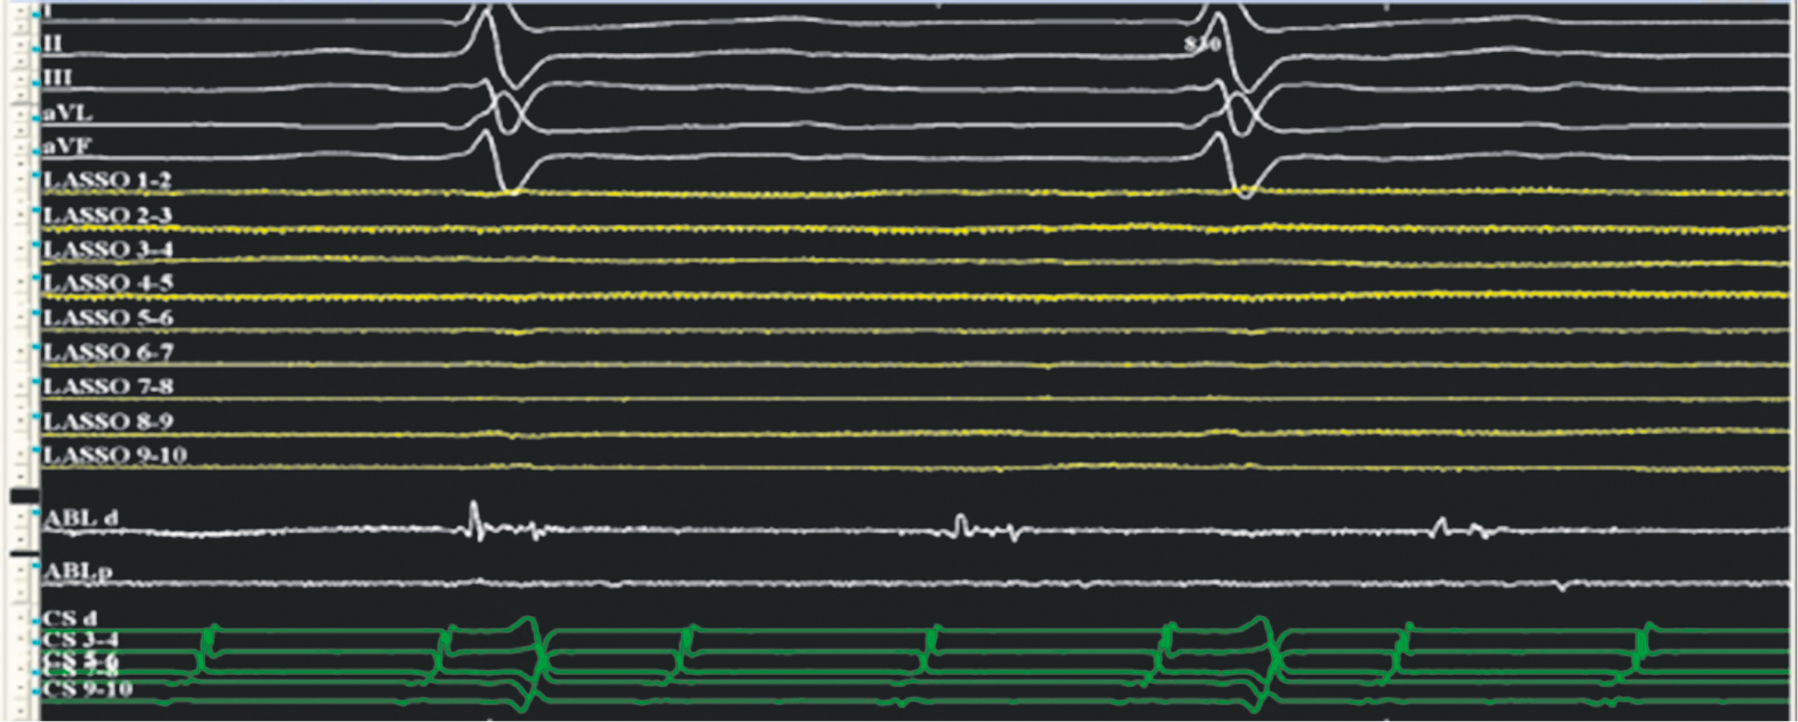

Fig. 7. Atrial flutter in a patient after labyrinth-3 surgery. Top–down: standard electrocardiogram leads, signals from a multipole circular electrode on the left atrial posterior wall (yellow), signals from the ablation electrode (white), ablation electrode located on a partially isolated site of the atrial myocardium, and signals from the multipole electrode in the coronary sinus (green). The EPT system “Claris” (Abbott, USA) was used. The recording speed was 200 mm/s

Рис. 7. Трепетание предсердий у пациента после операции лабиринт-3. Стрелками указаны низкоамплитудные фрагментированные сигналы. Сверху вниз: стандартные отведения электрокардиограммы, сигналы с многополюсного циркулярного электрода на задней стенке левого предсердия (желтые), сигналы с аблационного электрода (белые). Аблационный электрод расположен на частично изолированном участке миокарда предсердий, сигналы с многополюсного электрода в коронарном синусе (зеленые). ЭФИ-система «Claris» (Abbot, США). Скорость записи 200 мм/с